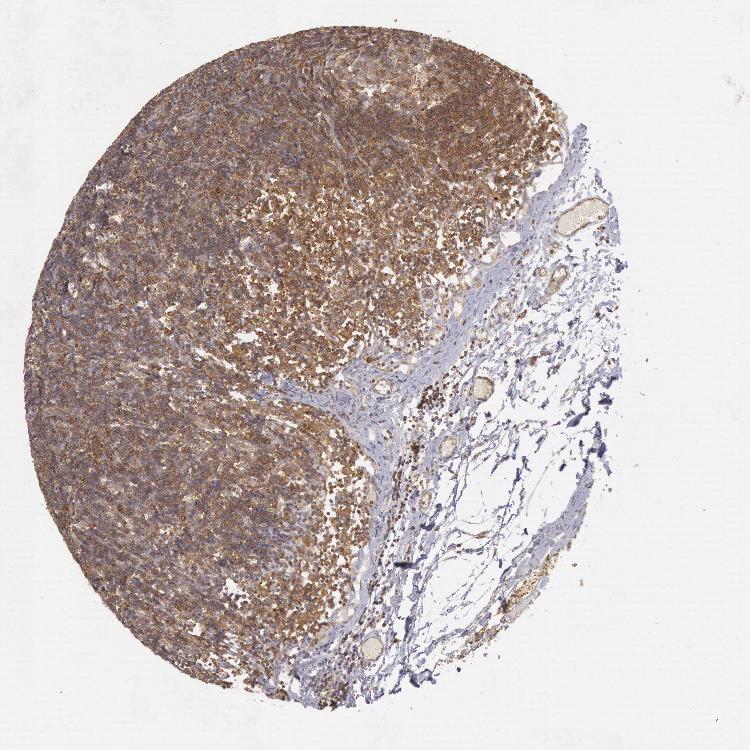

IKBKB